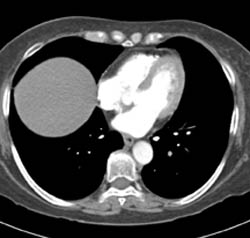

Diagnosis

Pe